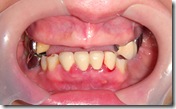

患者A先生

上顎 正面 下顎

患者B小姐

以上兩位患者口內狀況非常複雜,要制定一個好的治療計畫,

不只要考慮到患者的牙齒條件,

還要顧及患者意願、時間、金錢、評估可獲得的結果等等。

所以像這類型的Case 醫師通常在初步的溝通後會先做出一兩個不同的治療計畫,

再和患者解釋,了解患者接受程度。